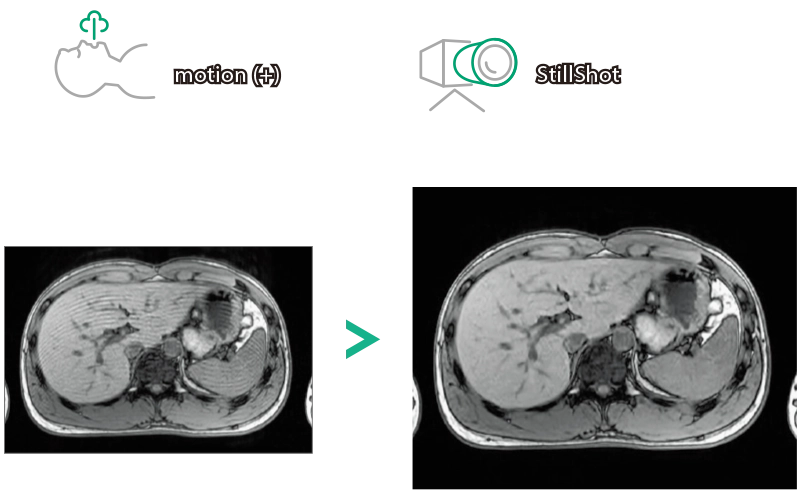

StillShot:The camera detects motion and suppresses the effects of body movement

T1WI Dual Echo (Out) Breath hold